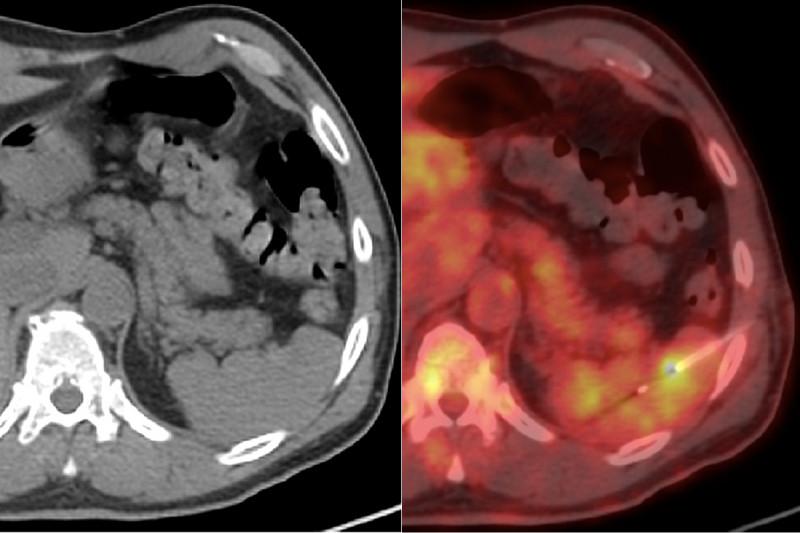

Dr. Meyers - book subject extraordinaire. New York University Medical Oncologist with a heart of gold #cycleoflives #stupidcancer